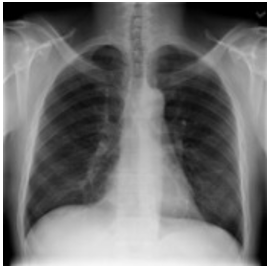

First: the performance metrices for the proposed edge detection technique is measured for healthy sample images using MATLAB and Zynq702 FPGA. The results of these performances are shown in Table 2 for 299×299 size images.

Table 2 and Table 3 illustrate both the healthy and infected images, respectivly, the clarity of edges is observed. The tables indicate that using the proposed method with MATLAB led to a significant improvement in edge clarity in the Infected images compared to the healthy ones. This is due to the characteristics of the COVID-19 disease present in the infected images, which increase the complexity of the edges and make them less clear. They also indicate that the images produced by the proposed method are clearer than those from MATLAB, as the proposed method employs fixed-point arithmetic to represent numbers that are closer to edge values than the numbers used by MATLAB, which relies on floating-point arithmetic.

Table 2. Results for normal images

Input Image

MATLAB Result

FPGA Result